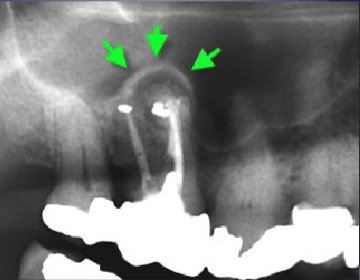

what’s the arrow pointing to

periosteal new bone formation

what are the arrows pointing to

“Halo sign”: elevation/displacement of max sinus floor